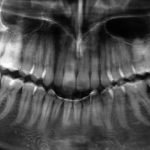

Autotrapianto di ottavo incluso a sostituzione di un settimo irrimediabilmente compromesso: case report

Riassunto

I trapianti dentali sono un capitolo...